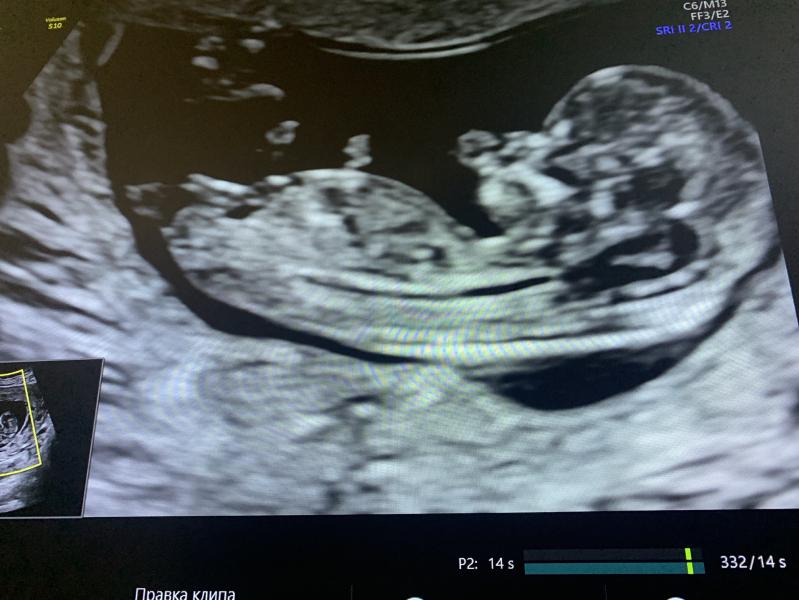

Девочка, половой бугорок вниз направлен (если конечно это он 😁)

Вот по бугорку вроде девочка и мне так кажется 😃